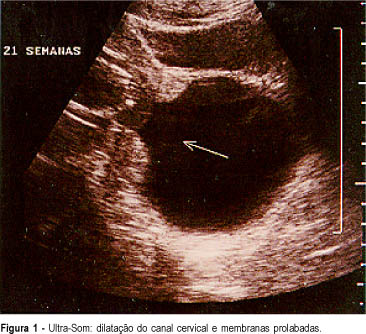

Ao US foi confirmada idade gestacional, a normalidade morfológica do concepto, a dilatação do canal cervical e a presença de membranas e líquido amniótico na vagina com a imagem de dilatação "em dedo de luva" ou "bico de mamadeira"